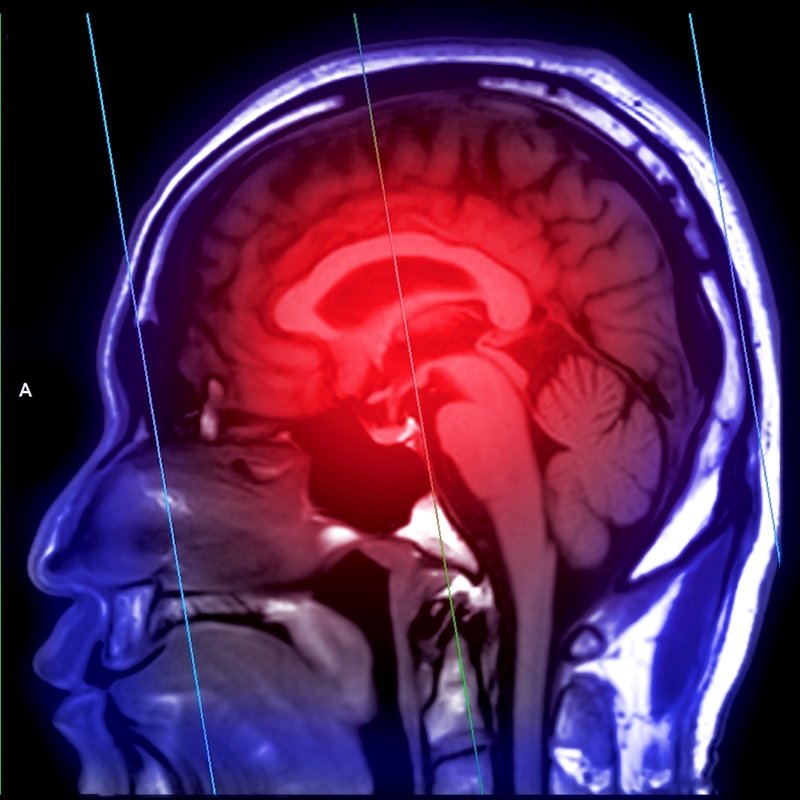

"Gençlerde inme olasılığı yükseliyor"

Dünya genelinde her yıl milyonlarca bireyi etkileyen ciddi sağlık sorunlarından biri olarak kabul edilen inme, Nöroloji uzmanı Dr. Vugar Jafar tarafından ele alındı. Dr. Jafar, inmenin tanımını "Acil bir beyin krizi" şeklinde yaparak, bu durumun ilerleyişini belirleyen en önemli faktörün erken müdahale olduğunu vurguladı. Beyne giden damarların birinin tıkanması sonucu meydana gelen inmenin, tıkanıklık sürecinde her geçen dakikada yaklaşık 1 milyon 900 bin nöronun ölümüne yol açtığını belirtti.